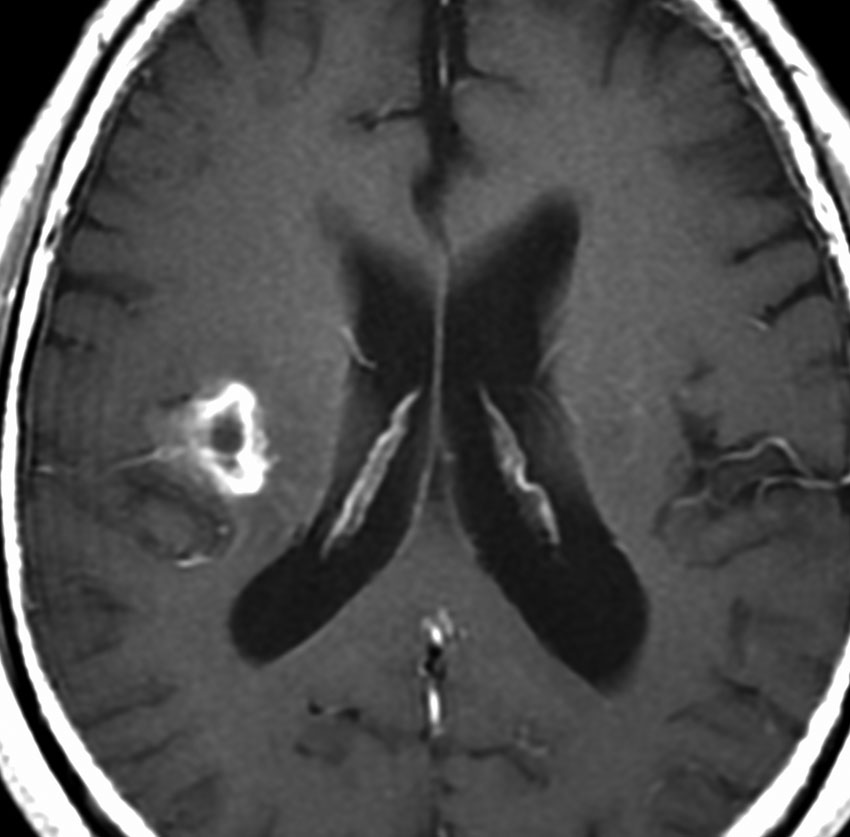

60代の患者さんの右前頭葉深部から島回に発生したものです。初発症状は症候性てんかんです。

ガドリニウム増強される腫瘍の中心部に壊死があり,悪性神経膠腫としては腫瘍周囲浮腫が強すぎるように見えるので,リンパ腫 PCNSLに似た画像所見です。